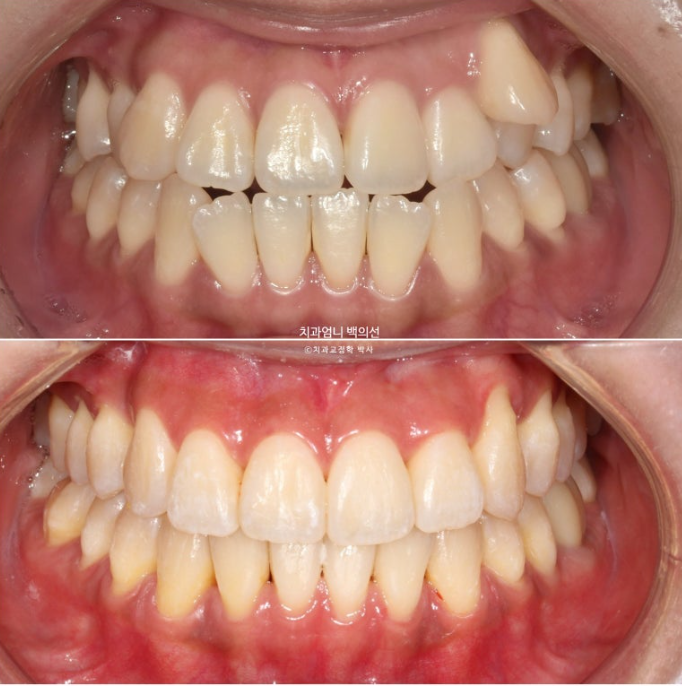

23.09~25.03

초진 3mm의 중심선 불일치가 해결되었습니다.

윗니가 아랫니를 덮는 양이 안정적입니다.

잘 내려와준 덧니입니다.

앞니가 거꾸로 물리던 부분도 정상교합을 찾았습니다